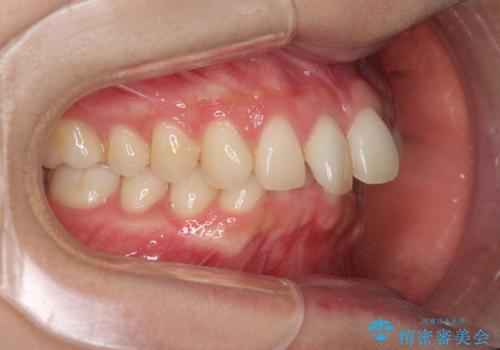

インビザラインによるディープバイトの改善

インビザラインによる上下歯列の遠心移動(後方移動)と、それに伴う近心傾斜(前方傾斜)の改善により、口元の突出感とディープバイトを改善することとしました。

咬合状態が大きく変化したため、治療後半では咬み合わせの位置が定まらなくなりました。上下の前歯に後戻り防止用のワイヤーを装着し、奥歯の咬合をフリーにしたことで1ヶ月ほどで咬み合わせが定まりました。